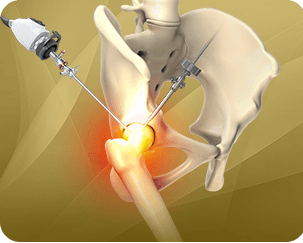

Direct anterior hip replacement is a minimally invasive hip surgery to replace the hip joint without cutting through any muscles or tendons as against traditional hip replacement that involves cutting major muscles to access the hip joint. This supports increased joint stability and reduces the need for hip precautions, allowing patients to get back to their activities sooner.